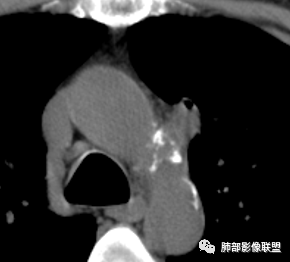

2019.08.24:胸部CT增强扫描:左肺上叶纵膈旁软组织结节影,双肺弥漫性小结节及细网状影,纵膈淋巴结肿大,心包积液,肝左叶散在低密度影。(没见片子)

2019年9月12日CT(外院片,手机拍摄)

现病史:患者于2个月前无明显诱因出现咳痰、咳痰,咳白粘痰或黄痰,有时痰中带血,伴发热,最高体温40.5度,多于下午起热,伴乏力盗汗,有时恶心呕吐,先后至日照市中心医院及青岛大学附属医院住院治疗,给予哌拉西林钠他唑巴坦及拜复乐抗炎,氟康唑抗真菌及对症支持治疗,患者入院检查痰培养(2019-09-08青岛大学附属医院)肺炎克雷伯菌。骨髓穿刺(2019-09-10青岛大学附属医院)检出1.5%异常浆细胞,胞浆kappa单克隆阳性。胸部CT(2019-08-24青岛大学附属医院)左肺上叶软组织影,双肺弥漫小结节并细网状影,纵膈淋巴结肿大,心包积液。自发病来,饮食睡眠差,体重较前下降约15斤。